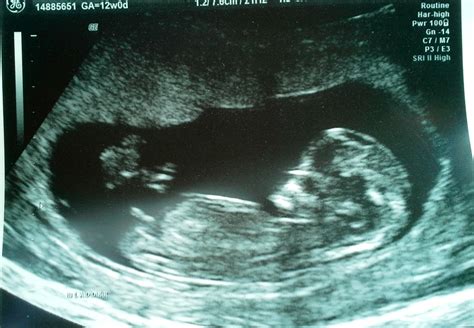

Pregnancy is an exciting journey filled with milestones, and one of the most anticipated is the 12 week ultrasound. This crucial scan provides valuable insights into the development of the fetus and the overall health of the pregnancy. Understanding what to expect during this ultrasound can help alleviate anxiety and prepare expectant parents for the experience.

A 12 week ultrasound, also known as the nuchal translucency scan, is typically performed between 10 weeks and 13 weeks and 6 days of pregnancy. This scan is essential for several reasons, including assessing the baby’s development, checking for any potential abnormalities, and measuring the nuchal translucency, which is the fluid-filled space at the back of the baby’s neck. This measurement is crucial for screening for chromosomal abnormalities such as Down syndrome.

The 12 week ultrasound is usually performed transabdominally, meaning the ultrasound probe is moved over the abdomen. In some cases, a transvaginal ultrasound may be used for better visualization, especially if the baby is positioned deeply in the pelvis.

During the procedure, the technician will apply a gel to the abdomen to enhance the transmission of sound waves. The probe will then be moved over the abdomen to capture images of the fetus. The entire process typically takes about 20-30 minutes.

During the 12 week ultrasound, several key measurements and assessments are made:

• Crown-Rump Length (CRL): This measurement from the top of the baby’s head to the bottom of the spine helps determine the gestational age and due date.

• Nuchal Translucency (NT): The thickness of the fluid-filled space at the back of the baby’s neck is measured. This measurement, along with maternal age and blood tests, helps screen for chromosomal abnormalities.

• Heartbeat: The baby’s heartbeat is checked to ensure it is within the normal range.

• Anatomy: The technician will look for the presence of the nasal bone, which is an important marker for Down syndrome. They will also check for the presence of both arms, legs, and the stomach bubble.